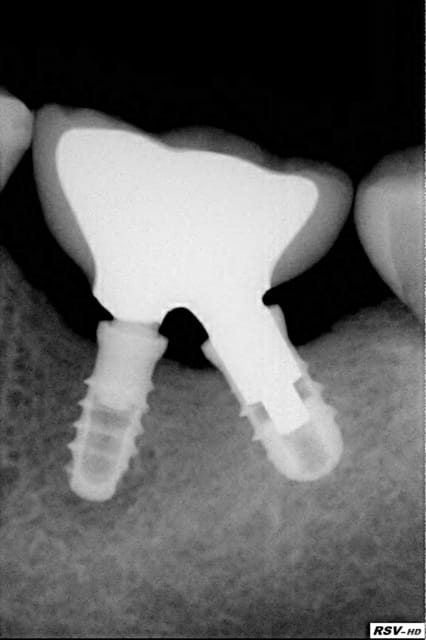

Maintenant pour rigoler regrader la rx jointe voilà où j'en suis avec Leone! Pour les détails prochaine conf le 13/10, si ça intéresse!

Sympa la radio

Tu as combien de recul sur ce cas ?

Tu impactes les 2 pilliers ?? L'axe étant différen, tu fais comment ?

J'aime bien le concept du vrai cone morse et pas de vis, mais j'aime pas la forme de l'impant (pas de vis) et la paroie du col me semble très mince....enfin, cé'est juste une impression sur les radio...

Trop peu! Il s"agit d'une tentative en accord avec le sujet. Juste un jeu pour le moment mais impossible avec tout autre système et si ça marche......

> Tu impactes les 2 pilliers ?? L'axe étant différen, tu fais comment ?

Simple chacun son tour; mais n'ayant pas de vis j'ai pu choisir et je n'ai fais qu'appliquer la mécanique.

> J'aime bien le concept du vrai cone morse et pas de vis, mais j'aime pas la

> forme de l'impant (pas de vis) et la paroie du col me semble très

> mince....enfin, cé'est juste une impression sur les radio...

Vrai et Faux. Avec son fm en place l'implant techniquement devient MONO-CORP.

C'est une question de repartition des forces (de la méca.)